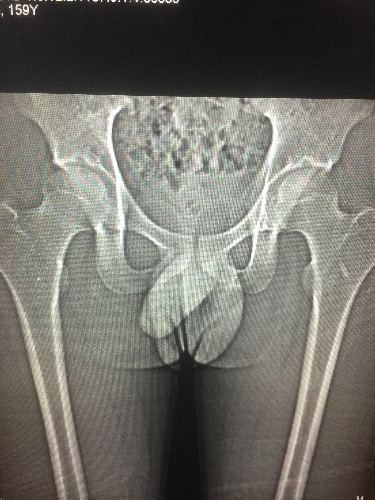

CT53395:髋关节

舞蹈系学生

双侧髋臼对称性骨质硬化,囊变,结合职业,考虑髋臼软骨损伤及软骨下骨囊变,做MR有意义。

双侧股骨头可见斑片状条片状高密度硬化,边缘较模糊。考虑:双侧股骨头缺血性坏死可能性大。建议MRI检查。